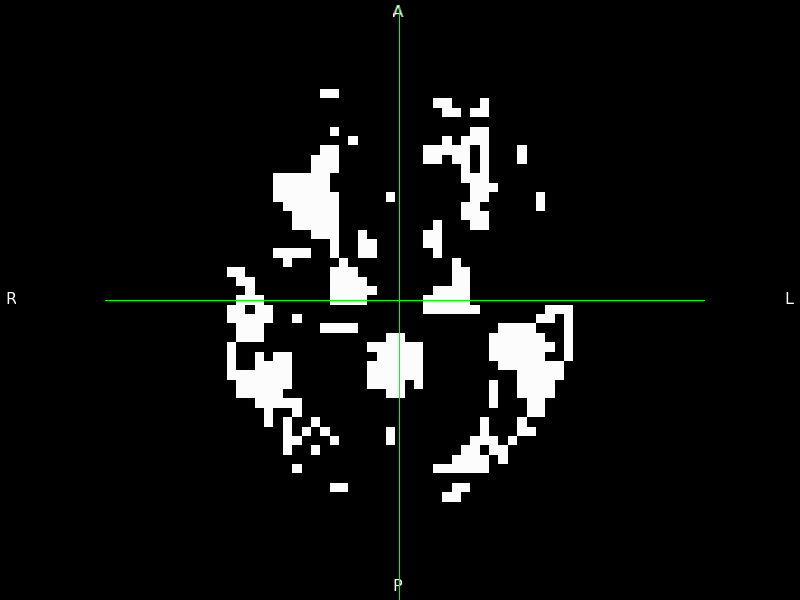

3.4.1 Pixel-level disease progression events in AMD

We apply the vEBM to OCT data from the DU cohort to reveal the first pixel-level sequence of disease events in AMD (Figure 6). The density of RPEDC spread around the centre of the eye reflects previous observations [62], and the vEBM provides a much finer-detailed progression pattern.

Refer to caption

Figure 6: Pixel-level disease progression sequence in AMD obtained by the vEBM. White pixels correspond to events that have occurred; black not yet occurred. We have selected 10 sequence positions at uniform steps of 50 across the total of 537 in the full sequence, with the top left figure corresponding to position 80 and the bottom right to position 530. Images were made from the vEBM output using 3D Slicer (https://www.slicer.org/).